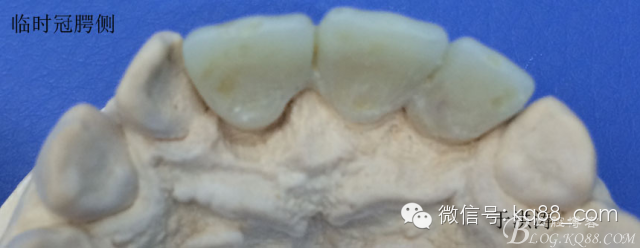

檢查:明顯可見22牙冠橫向斷裂至頸1/3處,近遠中與腭側斷裂至齦下??梢?/span>11牙冠斜向近中斷裂,近中與腭側均斷裂至齦下。21牙冠中1/3有裂痕。11 21 22松動(0),11 21叩(+),22叩(-),11 21 22探(-),11 21 22冷熱(-)。11 21 22唇側牙齦與粘膜和根尖相應部位未見明顯改變。11 22腭側牙齦增生性改變。11 21 22腭側粘膜和根尖相應部位未見改變。11 21 22舌側窩均有充填物。面部左右對稱無改變。余牙正常。(11,21,22牙冠顏色無改變)。 輔助檢查:X線片檢查11 22牙冠均有缺失。11 21 22 髓腔內均有充填物,11充填不到位, 21充填不實,22充填到位髓腔高密度影像。11 21 牙周膜有增寬,21根尖區(qū)有2mm左右低密度影像。未發(fā)現(xiàn)有牙根側穿或斷裂異物。 診斷:11,21慢性尖周炎,11,22殘冠。 治療計劃: 22無需治療。11 21 建議牙齒根管再治療。告知情況及費用。 1,11 21去除根充物。 2,11 21根管治療。 3,11 22纖維樁樹脂核修復。 4,高頻電刀去除11 22腭側牙齦組織到斷面。 5,11,21,22全瓷單冠修復牙齒。 治療過程:經(jīng)患者同意。H銼去除11 21原有充填物,未發(fā)現(xiàn)明顯滲出物,無異味。K銼疏通根管,VDW根測儀測量長度,11牙20mmWL,21牙20mmWL。S3鎳鈦器械預備根管。(全程1%次氯酸鈉沖洗EDTA溶解潤滑)試尖片顯示牙膠未到位,繼續(xù)向牙根尖各2mm進入預備。吸潮紙尖吸干根管,登士柏樹脂根充糊劑輸送至根尖部位,以測量數(shù)據(jù)用牙膠尖冷充側壓充填根管,3M玻璃離子封閉根管口。不可用患牙啃咬硬物,擇日冠修復。 輔助檢查:插針X線片顯示根管內充填物已經(jīng)取出。試尖片顯示牙膠尖未到位,繼續(xù)用K銼和機括向根尖預備。根充結束片顯示根充密實,無超充,無欠充。 醫(yī)囑:常規(guī)醫(yī)囑,不適隨診。 各步驟操作見下圖 于洪濤 2015.02.03 復 診 主訴:無疼痛,不適癥狀已經(jīng)消失。 檢查:11 21 充填物存在邊緣封閉完好,叩(-)松動(0)牙齦及周圍同初診。11 21 22無任何不適。 治療過程:由于患者自身原因即將兩個月來復診。拍X線片,去除11 22髓腔內部分牙膠,P鉆預備根管到達預定位置。粘結纖維樁,制作冠核。初預備11 21 22牙冠。高頻電刀按廠家要求功率和方法去除11 22腭側牙齦組織到達牙齒斷裂部位,調整檔位和功率繼續(xù)凝固和精修腭側組織,11 21 22排齦精修拋光。硅橡膠兩次法取模,可見模型完整肩臺清晰。制作臨時冠,科爾不含丁香油臨時冠粘結系統(tǒng)粘接。 模型送技師制作。預約義齒佩戴時間。(需術前牙齒比色) 輔助檢查:X線片顯示根尖低密度影像消失,牙周未見異常。X線片顯示纖維樁密合到位。 醫(yī)囑:不可用臨時牙肯咬硬物,不適隨診。 各步驟操作見下圖 于洪濤 2015.03.26 復 診 主訴:牙齒無癥狀,自感腭側術區(qū)舌舔粘膜不適。 檢查:臨時冠完整,無松動,邊緣緊密。牙齒無疼痛,唇側牙齦無明顯紅腫,腭側牙齦愈合良好,牙冠肩臺邊緣清晰。腭側牙齦術區(qū)中度觸及有少量滲血。 治療過程:義齒制作完成。去除臨時冠及粘結物。義齒試戴調整完全就位,無懸突,無縫隙。清洗義齒,氫氟酸處理義齒50秒(加強醫(yī)患防護),沖洗吹干,偶聯(lián)劑處理備用。基牙37%酸處理15秒,沖洗吹干,隔濕,排齦,涂第五代粘結劑。小蜜蜂雙固化樹脂水門汀激活攪拌注入義齒中,按順序就位,加壓力,牙線去除牙縫隙多余樹脂,涂阻氧劑,基牙唇腭側各光照固化3秒之后去除多余水門汀取出排齦線,繼續(xù)光照固化牙齒每個面20秒。精細查找去除多余水門汀。 醫(yī)囑:1,患牙咀嚼硬物加以注意。 2,常規(guī)醫(yī)囑,不適隨診,。 3,加強口腔衛(wèi)生意識。定期復診檢查。 各步驟操作見下圖 于洪濤 2015.04.07 回訪病例 主訴:咀嚼食物非常自如,無任何不適。 檢查:義齒牙體完整。無松動,無叩痛。唇側牙齦紅潤質韌無萎縮,腭側術區(qū)牙齦愈合良好,無炎癥改變。唇腭側根尖相應部組織無改變。余牙正常。 輔助檢查:X線片顯示牙根及周圍未見異常。未見骨萎縮。牙冠及頸部未見異常。 醫(yī)囑:定期檢查義齒,不適隨診。 各步驟操作見下圖 于洪濤2015.04.28